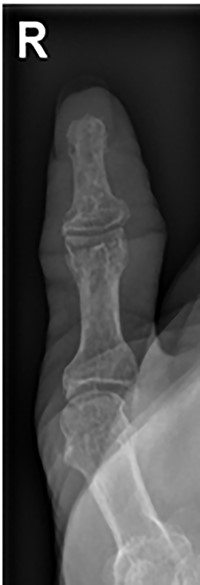

The patient was then reviewed 6 weeks after her initial presentation, following the results of the sarcoma MDT, which confirmed a benign tumour. At this point, the patient reported some tenderness around the surgical incision, but that her symptoms were improving. It was thought that she had no signs of ongoing infection in the thumb. The outcome was for monitoring of her symptoms with no indication for surgical excision. She had a follow-up X-ray in 6 weeks’ time that showed resolution of the lytic lesion (Figs 6 and 7).

AP follow-up radiograph of right thumb 6 weeks post-admission showing resolution of lytic lesion.

Lateral follow-up radiograph of right thumb 6 weeks post-admission showing resolution of lytic lesion.